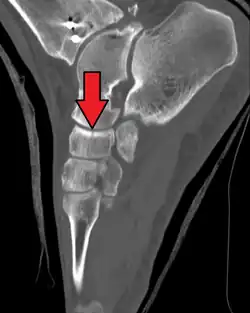

Fracture of the navicular bone

The human navicular is not a commonly broken bone but it breaks due to two reasons. The first mechanism is a stress fracture which happens commonly in athletes,[7] and the other mechanism is a high energy trauma.

The navicular bone is a keystone of the foot: it is part of the coxa pedis and articulates with the talus, first, second and third cuneiform, cuboid and calcaneus. It plays an important role in the biomechanics of the foot, helping in inversion, eversion, and motion; it is a structural link between midfoot and forefoot and it is part of the longitudinal and transverse arch of the foot.